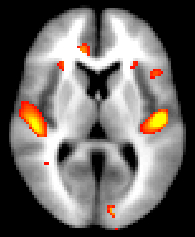

Obtaining and displaying your FSL-VBM results

We strongly recommend using randomise (permutation testing) for inference in VBM-style analysis and not Gaussian random field theory (GRF), as the approximations underlying the latter are not generally appropriate in such analyses.

Running randomise and displaying TFCE-based thresholding results

You can then view the (1-p) corrected p-value images in FSLView:

Running randomise and displaying cluster-based thresholding results

Once you have chosen the most appropriate smoothing (e.g. sigma = 3mm) and threshold (e.g. t > 2.3) for the cluster-based correction, then feed them into a full run of randomise (see randomise usage), for instance:

Then you can threshold your _clustere_corrp_ images (corrected p-values maps) at 0.95 to keep only the significant clusters and use it to mask the corresponding tstats map:

fslmaths fslvbm_clustere_corrp_tstat1 -thr 0.95 -bin mask_pcorrected

fslmaths fslvbm_tstat1 -mas mask_pcorrected fslvbm_tstat1_corrected

before displaying it with fsleyes overlaid on the template_GM or the MNI152 template for example: